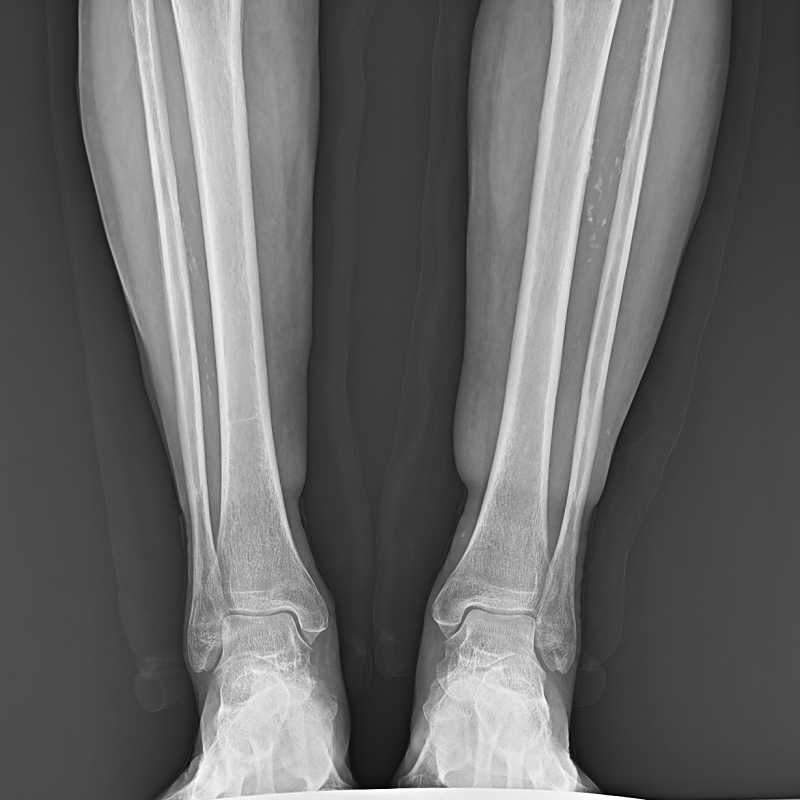

●呈現全下肢或全脊柱圖像

●在脊柱及下肢畸形矯正手術治療中,為術前方案制定和術后復查提供精準測量

●有效解決傳統X光片不能一次成像問題,為患者提供更加優質的醫療服務